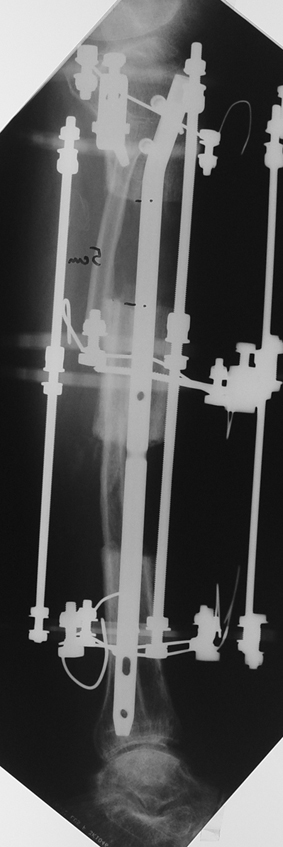

The duration of external fixation (external fixation index) depends on the amount of distraction required, and the extremity is prone to complications during this period. After the distraction phase is completed, the external fixator remains in place during the consolidation phase, which lasts twice as long as the distraction phase; but this period is hardly tolerated. If the external fixator is removed before sufficient consolidation is achieved, fractures, deformity and shortness will be the result. In our department, ‘lenghthening over nail’ method is used in order to decrease the external fixation index and increase patient comfort and activity level. In this method, the intramedullary nail is statically locked after the completion of the distraction phase, and external fixator is removed. The extremity is stabilized by the intramedullary nail during consolidation phase. In this way, complications due to long external fixation index or early removal of the external fixator are avoided.